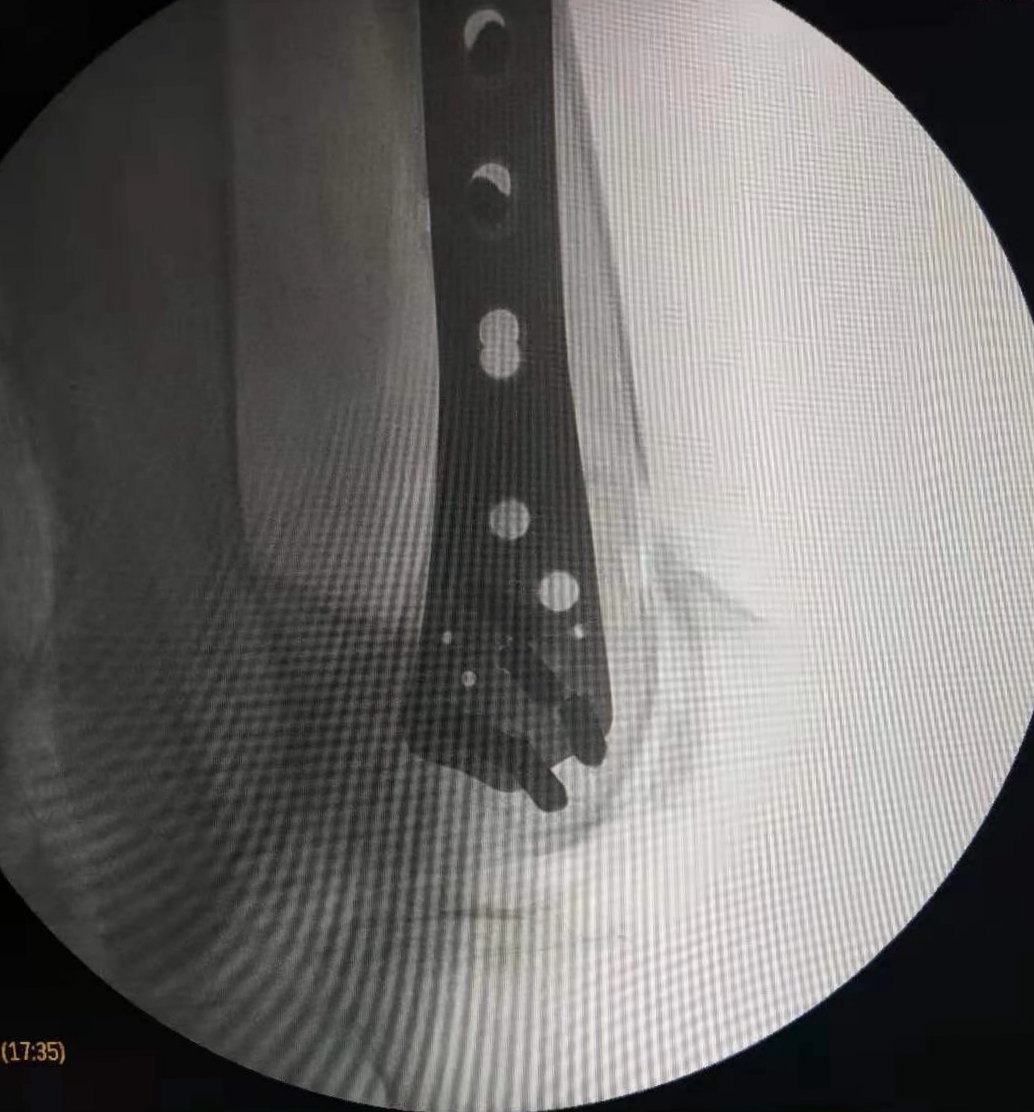

在这个寒冷的初冬,昨日21点玩法研究所 骨二科收治了一名特殊的患者,我院88岁高龄退休老专家,老人在家摔伤导致股骨髁上粉碎性骨折,拒绝去家附近的大21点游戏规则 ,专程来我院骨二科就诊。

郭华副院长、张延平主任对病人进行了详细、全面的查体分析,因患者年龄较大,骨折严重再加上老年骨质疏松,骨折部位极易损伤后方血管,考虑患者病情的特殊性,骨二科拟行急诊手术治疗。术前,对患者进行了全面、细致的手术风险及效果评估,按照我科老年患者的优化诊疗标准流程,制定了精准的手术方案,包括风险预案、围手术期准备及护理措施,准备完成后,在急诊进行手术治疗,手术历时2小时。手术顺利、安全完成,目前患者在我科积极术后康复治疗。